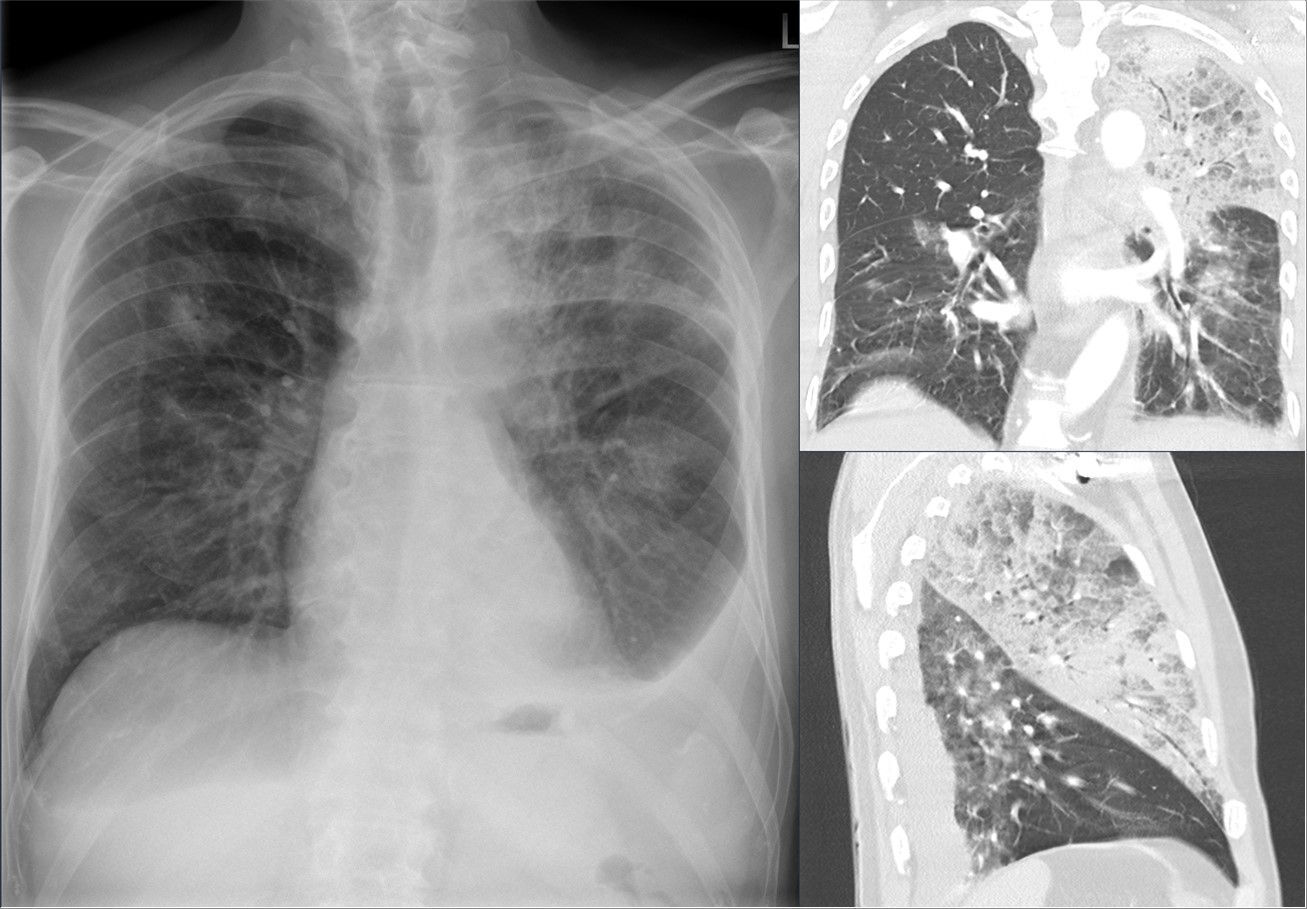

Доктор Екатерина Демьяновская перечислила симптомы, при которых можно заподозрить туберкулез еще до флюорографии, пишет Life.ru.

Поздняя диагностика заболевания значительно влияет на качество лечения. Выявить патологию на ранней стадии помогает ежегодный профосмотр. Симптомами туберкулеза являются слабость и продолжительный кашель, который беспокоит пациента без других признаков простуды.

Насторожить должны быстрая утомляемость, повышение температуры до 37,5 градусов, чрезмерная потливость по ночам, боль в груди, одышка и снижение аппетита. У больного также снижается вес.

Фото: commons.wikimedia.org, Hellerhoff, Creative Commons Attribution-Share Alike 4.0 International license.